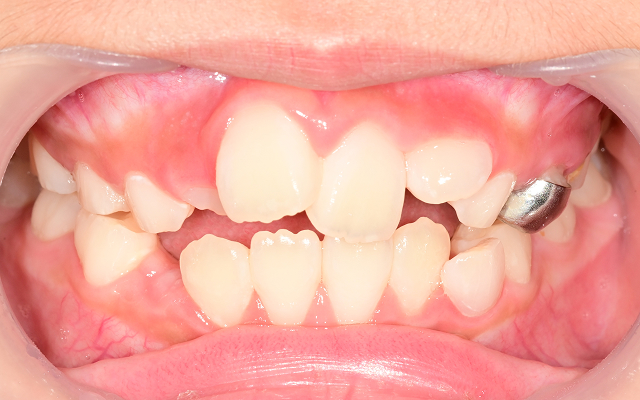

성장기 교정 시기를 놓치면 생길 수 있는 문제

• 01

턱뼈의 성장이 비대칭으로 진행되어 성인 교정 시 수술이 필요할 수도 있음(양악수술)

• 02

영구치가 덧니로 나거나 발치가 필요한 경우로 악화(발치교정)

• 03

교합 불균형으로 턱관절 통증, 비대칭 얼굴선이 생길 수 있음

• 04

입으로 호흡하는 습관이 고착되어 얼굴형이 길어짐